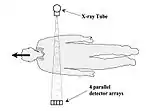

- Scanning speed increases for volume imaging subsequently generated technical advances such as multi-detector scanning (MDCT). Initially, about year 1998, four slices of thickness 0.5-10 mm were able to be scanned simultaneously using a 2D detector array with a z-axis length of 20-32 mm - see Figure 7.15.7. Scanner rotation times of half a second or less were achieved by mounting the XRT, the HV generator and the detector array on the same rotating gantry, for instance. The speed improvements, along with reductions in tube loading, were found to result in only a modest increase in patient dose. On this basis, techniques such as ECG-gated cardiac studies, coronary artery calcification scoring, Virtual Colonoscopy and CT Angiography (CTA) were developed.

Fig. 7.15.7: Illustration of 4-slice CT.